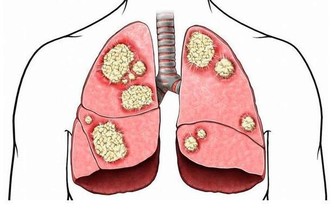

對於男性的前列腺來說,最怕遇到的就是前列腺充血的情況,因為這往往會誘發前列腺炎或是前列腺癌。